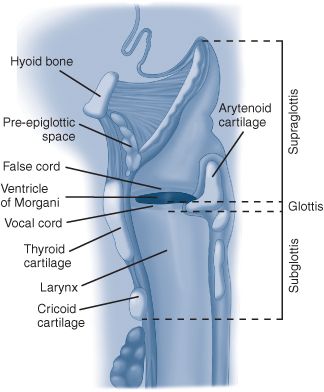

Lymphatic drainage of the larynx is distinct for each subsite. Two major groups of laryngeal lymphatic pathways exist: those that drain areas superior to the ventricle, and those that drain areas inferior to it. Supraglottic drainage routes pierce the thyrohyoid membrane with the superior laryngeal artery, vein, and nerve, and drain mainly to the subdigastric and superior jugular nodes. Those from the glottic and subglottic areas exit via the cricothyroid ligament and end in the prelaryngeal node (the Delphian node), the paratracheal nodes, and the deep cervical nodes along the inferior thyroid artery. Limited glottic cancers typically do not spread to regional lymphatics (1 to 4%). However, there is a high incidence of lymphatic spread from supraglottic (30 to 50%) and subglottic cancers (40%). (See Schwartz 9th ed., p 498, and Fig. 18-2.)

FIG. 18-2. Sagittal view of the larynx with the divisions of the supraglottis, glottis, and subglottis demonstrated.